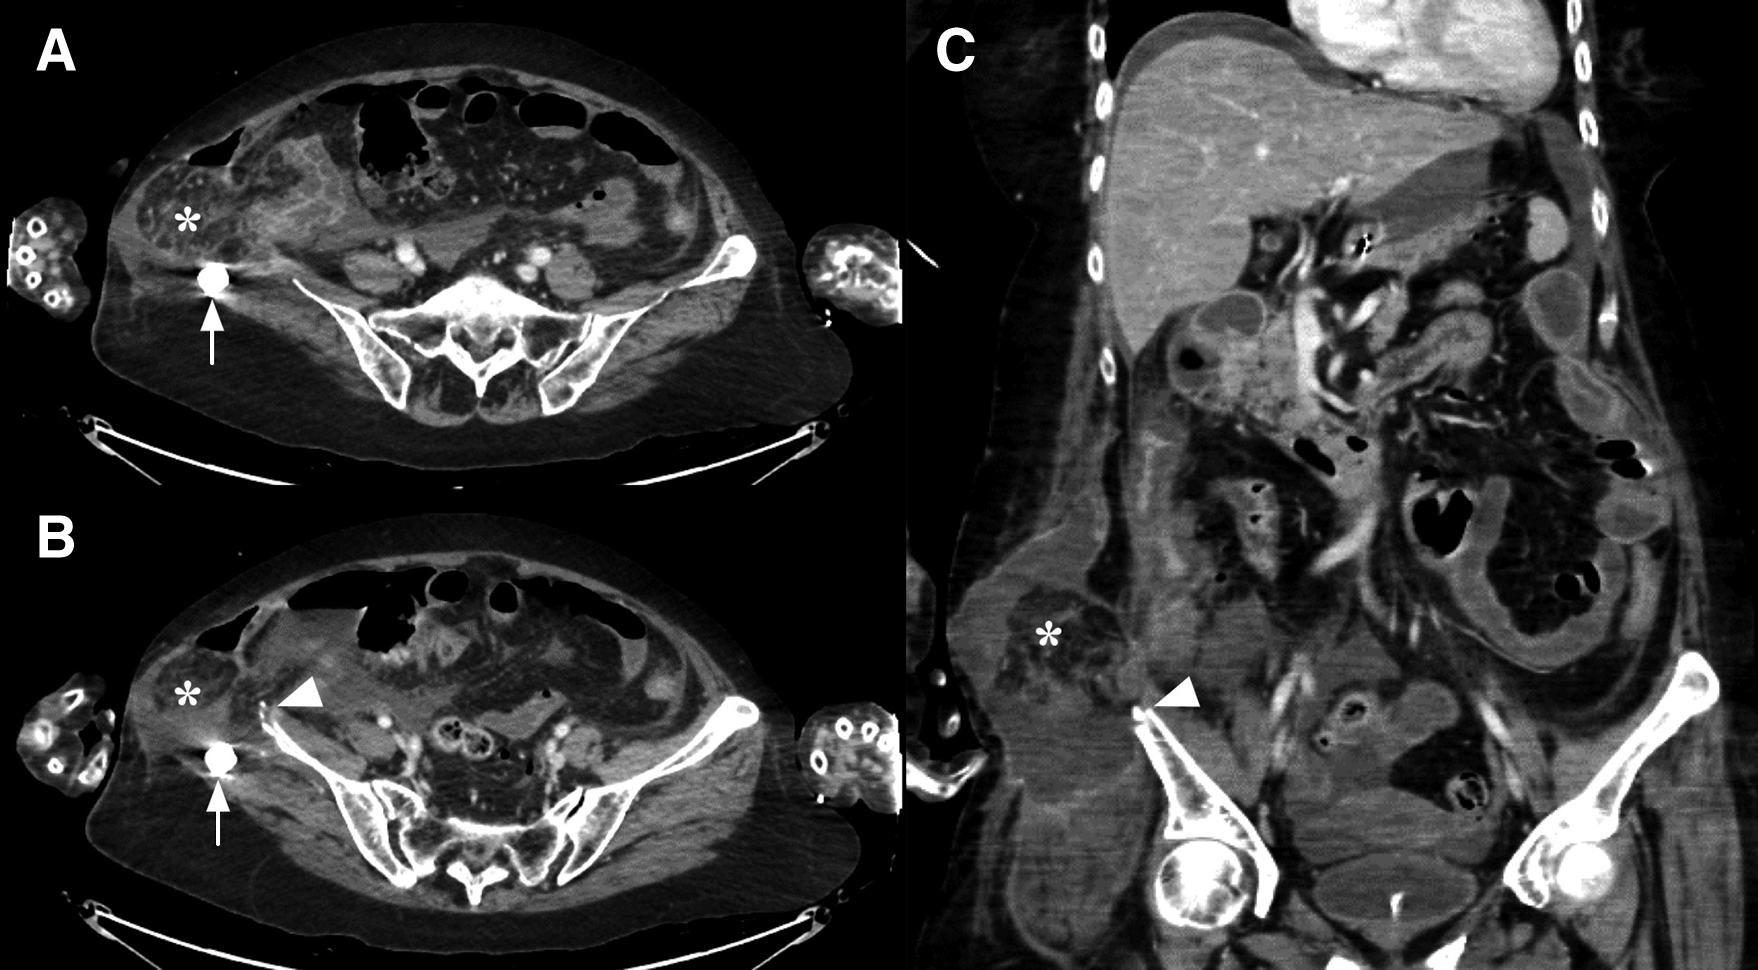

腹部造影CT所見:腹水の貯留および腹腔内フリーエアーを認めた.腸骨片採取部の頭側の右側腹部に横行結腸が脱出し,腹水が貯留しており,ヘルニア嵌頓と診断した.ヘルニアは約10 cm大であった.嵌頓している腸管の造影効果は不良であり,腸管の壊死が示唆され,同部位で消化管が穿孔している可能性が疑われた.また,ヘルニア囊内に腸骨片採取後の右腸骨骨折部骨端が突出している所見を認めた(Fig. 2).ヘルニアの頭側端は第12肋骨から2 cm尾側まで,尾側端は腸骨上縁から8 cm尾側まで及んでいた.

Enhanced CT findings before operation. A: Enhanced CT revealed ascites fluid and free air. There was a right lumbar hernia and transverse colon was incarcerated into the right lumbar hernia. Transverse colon was not enhanced well, and this finding suggested that transverse colon would be necrotic (asterisk). Arrow showed cement spacer replaced at bone graft. B: Arrowhead shows bone end of the right iliac wing after autogenous graft projecting in the right lumbar hernia. C: Coronal section image of enhanced CT revealed the right lumbar hernia. The transverse colon and ascites fluid were incarcerated into the right lumbar hernia.